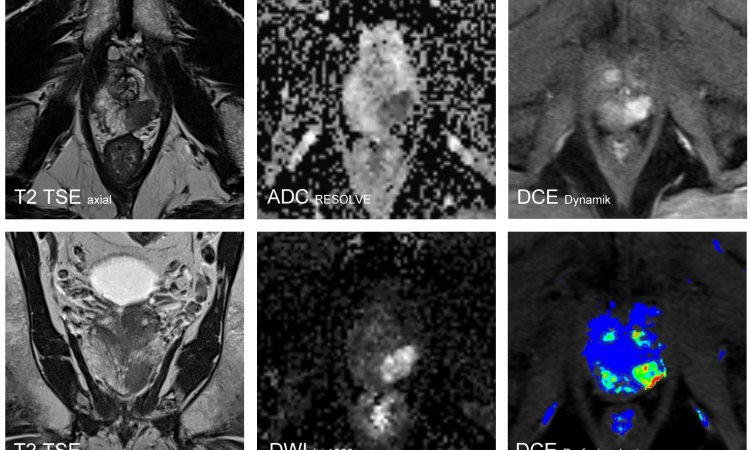

Als derzeit führendes Verfahren, um die Prostata darzustellen, gilt die multiparametrische MRT. Dabei werden morphologische Bilddaten um funktionelle Parameter ergänzt. „Funktionell bedeutet in diesem Fall zunächst einmal das Diffusionsverhalten im Gewebe“, erklärt Dr. Röthke. „Tumoren zeichnen sich durch eine hohe Zellteilungsrate aus. Wenn man sie unter dem Mikroskop betrachtet, sieht man, dass das Gewebe aus vielen großen Zellkernen und wenig Zytoplasma besteht. Dementsprechend misst man bei der diffusionsgewichteten MRT, dass sich die Wassermoleküle in diesem Gewebe weniger frei bewegen können.“ Ein weiteres funktionelles Kriterium, das mithilfe von Kontrastmitteldynamiken untersucht wird, ist das Perfusionsverhalten. Denn auch die Durchblutungsmuster von Tumoren unterscheiden sich von denen in gesundem Gewebe.